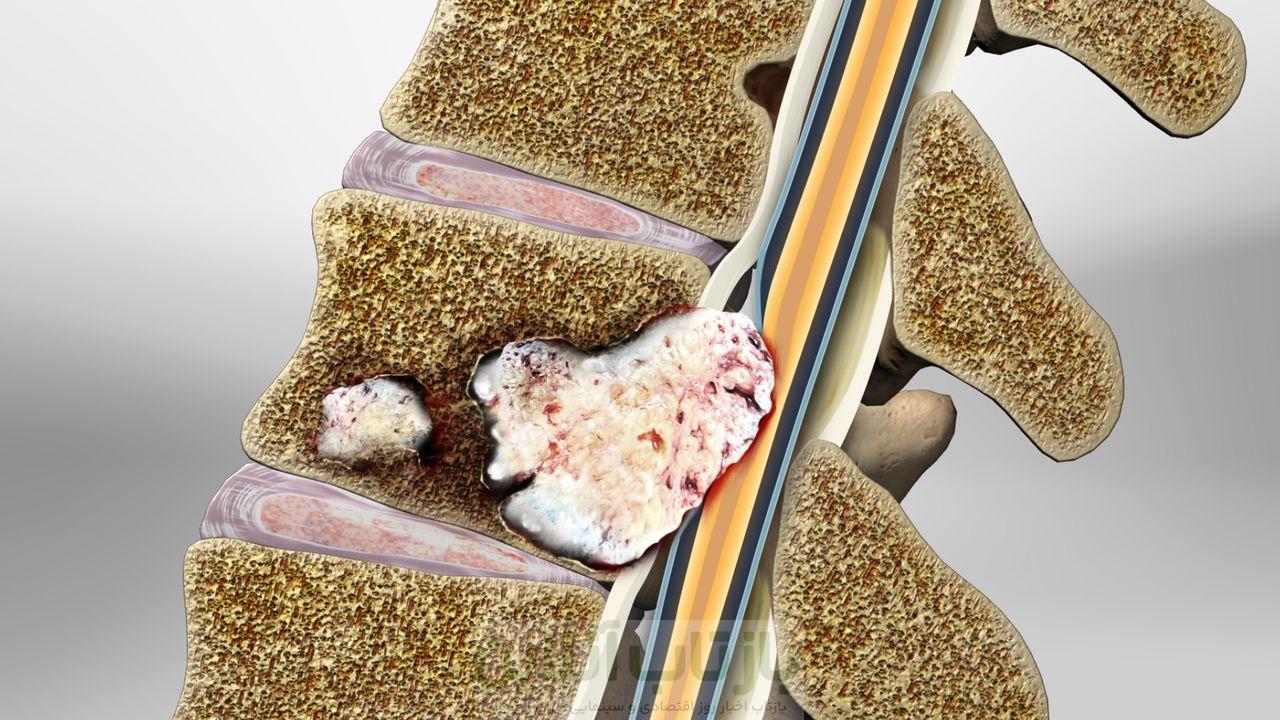

سرطان ستون فقرات به رشد غیرطبیعی و کنترلنشده سلولها در ناحیه ستون فقرات گفته میشود. این بیماری را میتوان به دو دسته اصلی تقسیم کرد:

- سرطان اولیه ستون فقرات: در خود ستون فقرات شکل میگیرد و نسبتا نادر است

- سرطان متاستاتیک ستون فقرات: شایعتر است و زمانی که سرطان از سایر قسمتهای بدن مانند پستان، ریه یا پروستات به ستون فقرات گسترش مییابد، رخ میدهد

- آسیب عصبی: فشار تومور روی نخاع یا ریشههای عصبی میتواند باعث درد، ضعف، بیحسی یا فلج شود

- شکستگی مهرهها: تومور میتواند استخوانها را تضعیف کند و منجر به شکستگی آنها شود

- ناپایداری ستون فقرات: میتواند باعث تغییر شکل ستون فقرات شود